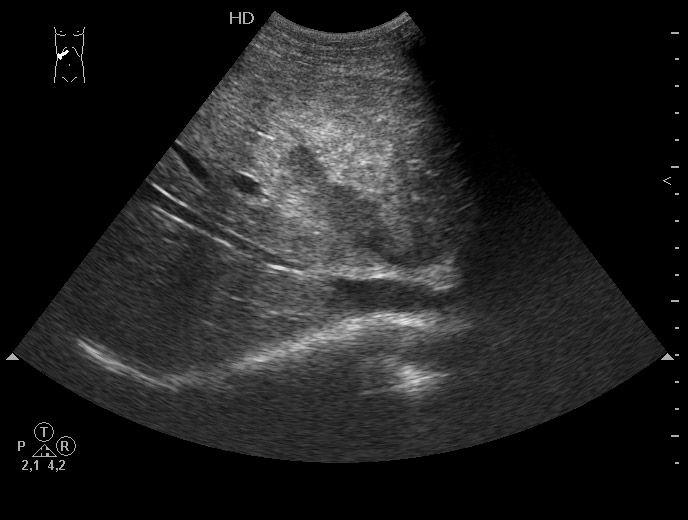

Все верно, разрыв печени плюс жидкость в боковом синусе плевральной полости.

Ультразвуковая семиотика разрыва довольно типична. Разместить эту сонограмму решил после того, как увидел протокол из одной авторитетной клиники, где гемангиома была трактована как разрыв печени и внутрипеченочная гематома.

Добавлю еще пару случаев

Краевой разрыв с гемоперитонеумом (вне поля сканирования)